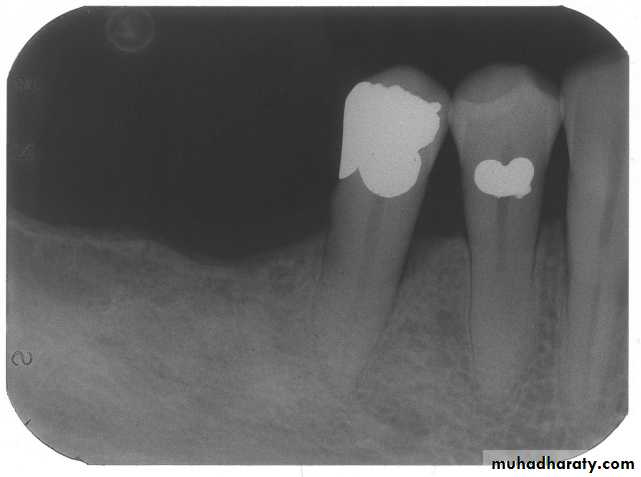

b. Radiographic examination

Panoramic radiograph, OPGPeriapical

Bitewing

9